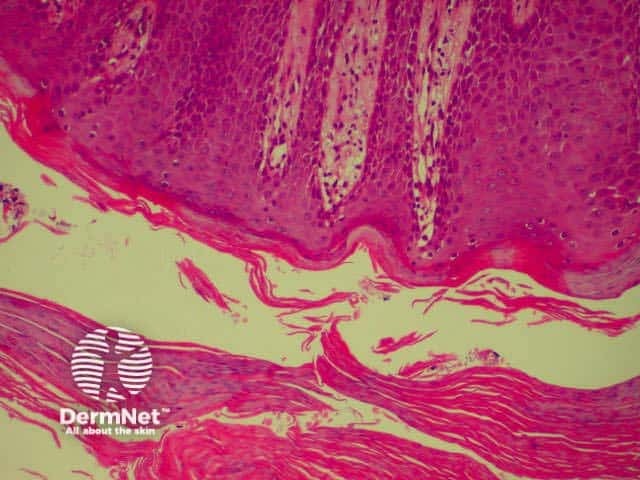

Bullous pemphigoid is the most common subepidermal blistering disease. Link to a clinical description of bullous pemphigoid.

The histological features of bullous pemphigoid are:

Direct immunofluorescence reveals IgG and complement deposits in the basement membrane zone. (Biopsies for fluorescence should ideally be taken from erythematous but not yet bullous areas.) Indirect immunofluorescence will detect circulating antibodies. ELISA will be positive to 180 and 230kd BP antigens 2 and 1 respectively. Using skin separated by a salt splitting process, immunoreactants are seen to bind to the roof of the blister.

Bullous pemphigoid Bullous pemphigoid Bullous pemphigoid